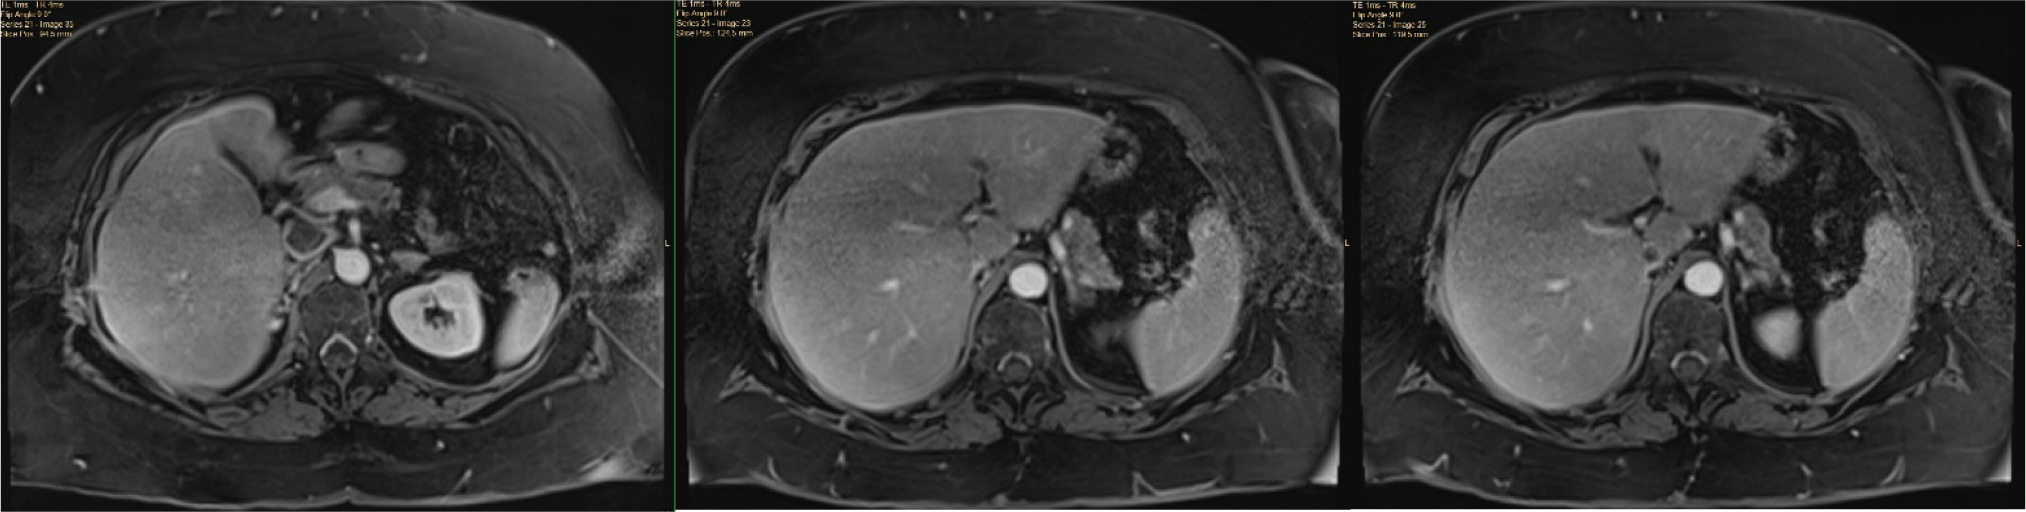

Transesophageal echocardiography (TEE) at the beginning of the operative procedure showed normal heart function with no RV dilation or evidence of emboli. TEE access was maintained throughout the case.

A standard chevron and retroperitoneal exposure were performed (5). Due to the friable tip of the thrombus (Figure 2), a decision was made to approach this as a level III tumor thrombus with suprahepatic control to avoid the extensive IVC manipulation required to release significant portions of the caudate and obtain an infrahepatic clamp (5). Suprahepatic circumferential control of the IVC was obtained along with the left renal vein and infrarenal IVC.

Figure 2: Pre-operative TEE showing friable thrombus tip.

After IVC control was obtained, attempts were made to ligate the right renal artery in the interaortocaval space (5). There was some difficulty visualizing the right renal artery due to tumor-related desmoplastic reaction and the patient’s obesity. During this dissection, the patient became hypotensive with systolic pressures in the 70s. This prompted the urologic surgeon (SD) to request TEE review, which revealed tumor thrombus filling most of the right atrium (Figure 3).

Figure 3: Intraoperative TEE showing tumor thrombus in the right atrium.